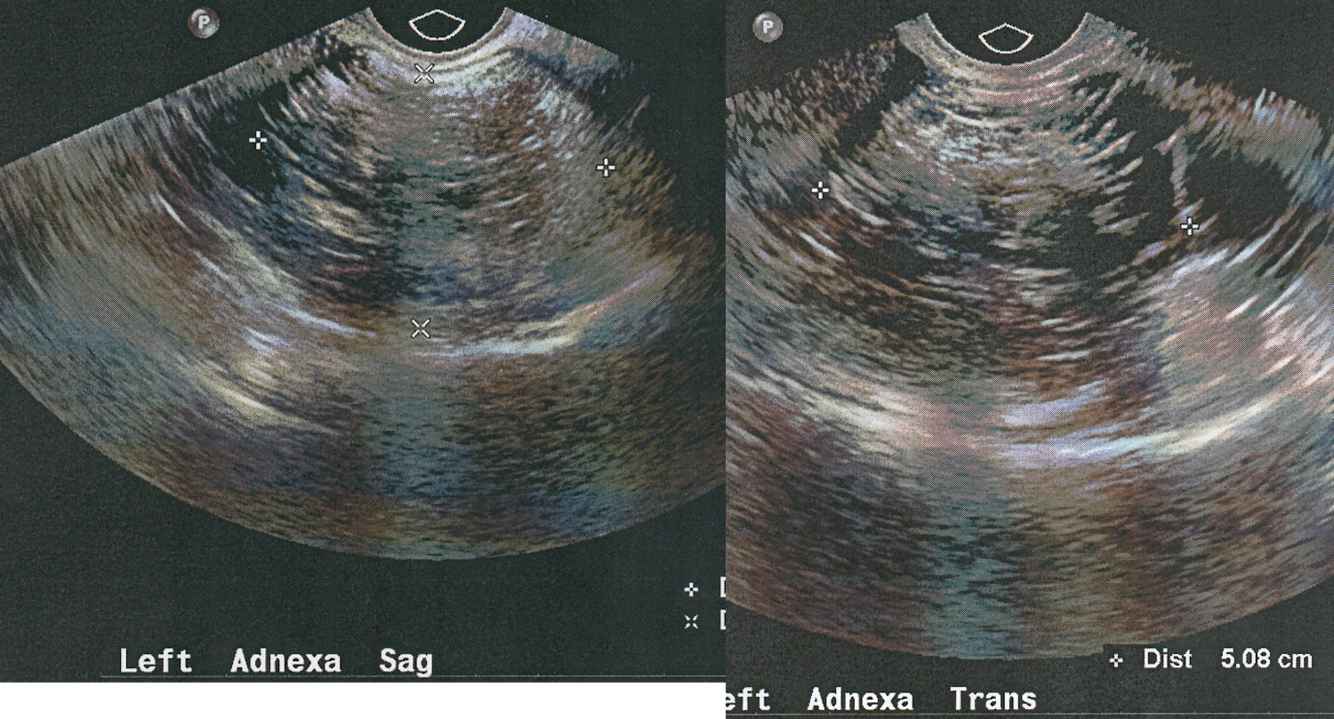

Dermoid Tumor

-dermoid mesh